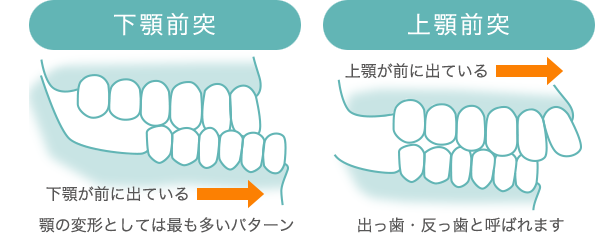

顎変形症とは上顎(上顎骨)や下顎(下顎骨)の形や大きさの異常、両者のバランスによる咬み合わせの異常(咬合不正)と顔の変形などの症状を示すものです

下あごが前に出ている『受け口』や『しゃくれ』、上あごが著しく突出している『出っ歯』などは顎変形症の症状の一つです。

受け口やしゃくれは歯科用語で『下顎前突(かがくぜんとつ)』『反対咬合(はんたいこうごう)』、出っ歯は『上顎前突(じょうがくぜんとつ)』と言います。

歯だけがでている状態を【下顎前突】や【上顎前突】と言い、骨から出ている状態を【骨格性(こっかくせい)下顎前突】と【骨格性上顎前突】といいます。